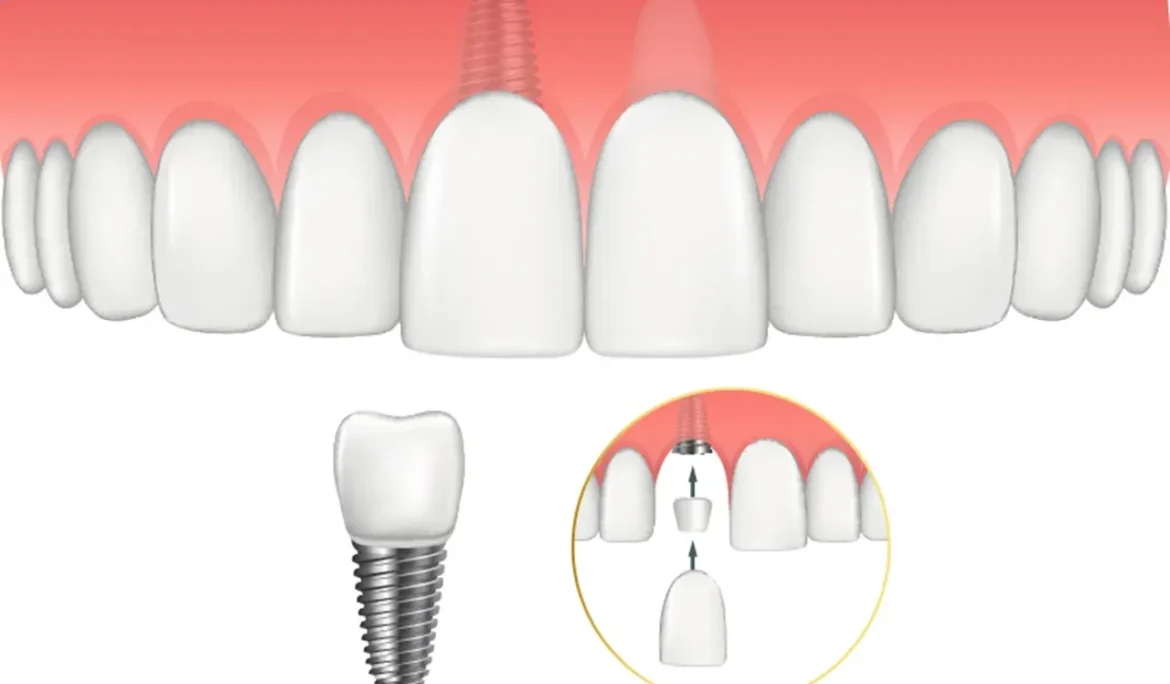

Gãy răng cửa là vấn đề phổ biến nhưng lại gây ảnh hưởng rất lớn đến thẩm mỹ khuôn mặt và sức khỏe răng miệng. Răng cửa

Ghép xương trong implant là một trong những kỹ thuật quan trọng giúp cải thiện chất lượng và độ bền của răng cấy ghép, đặc biệt khi